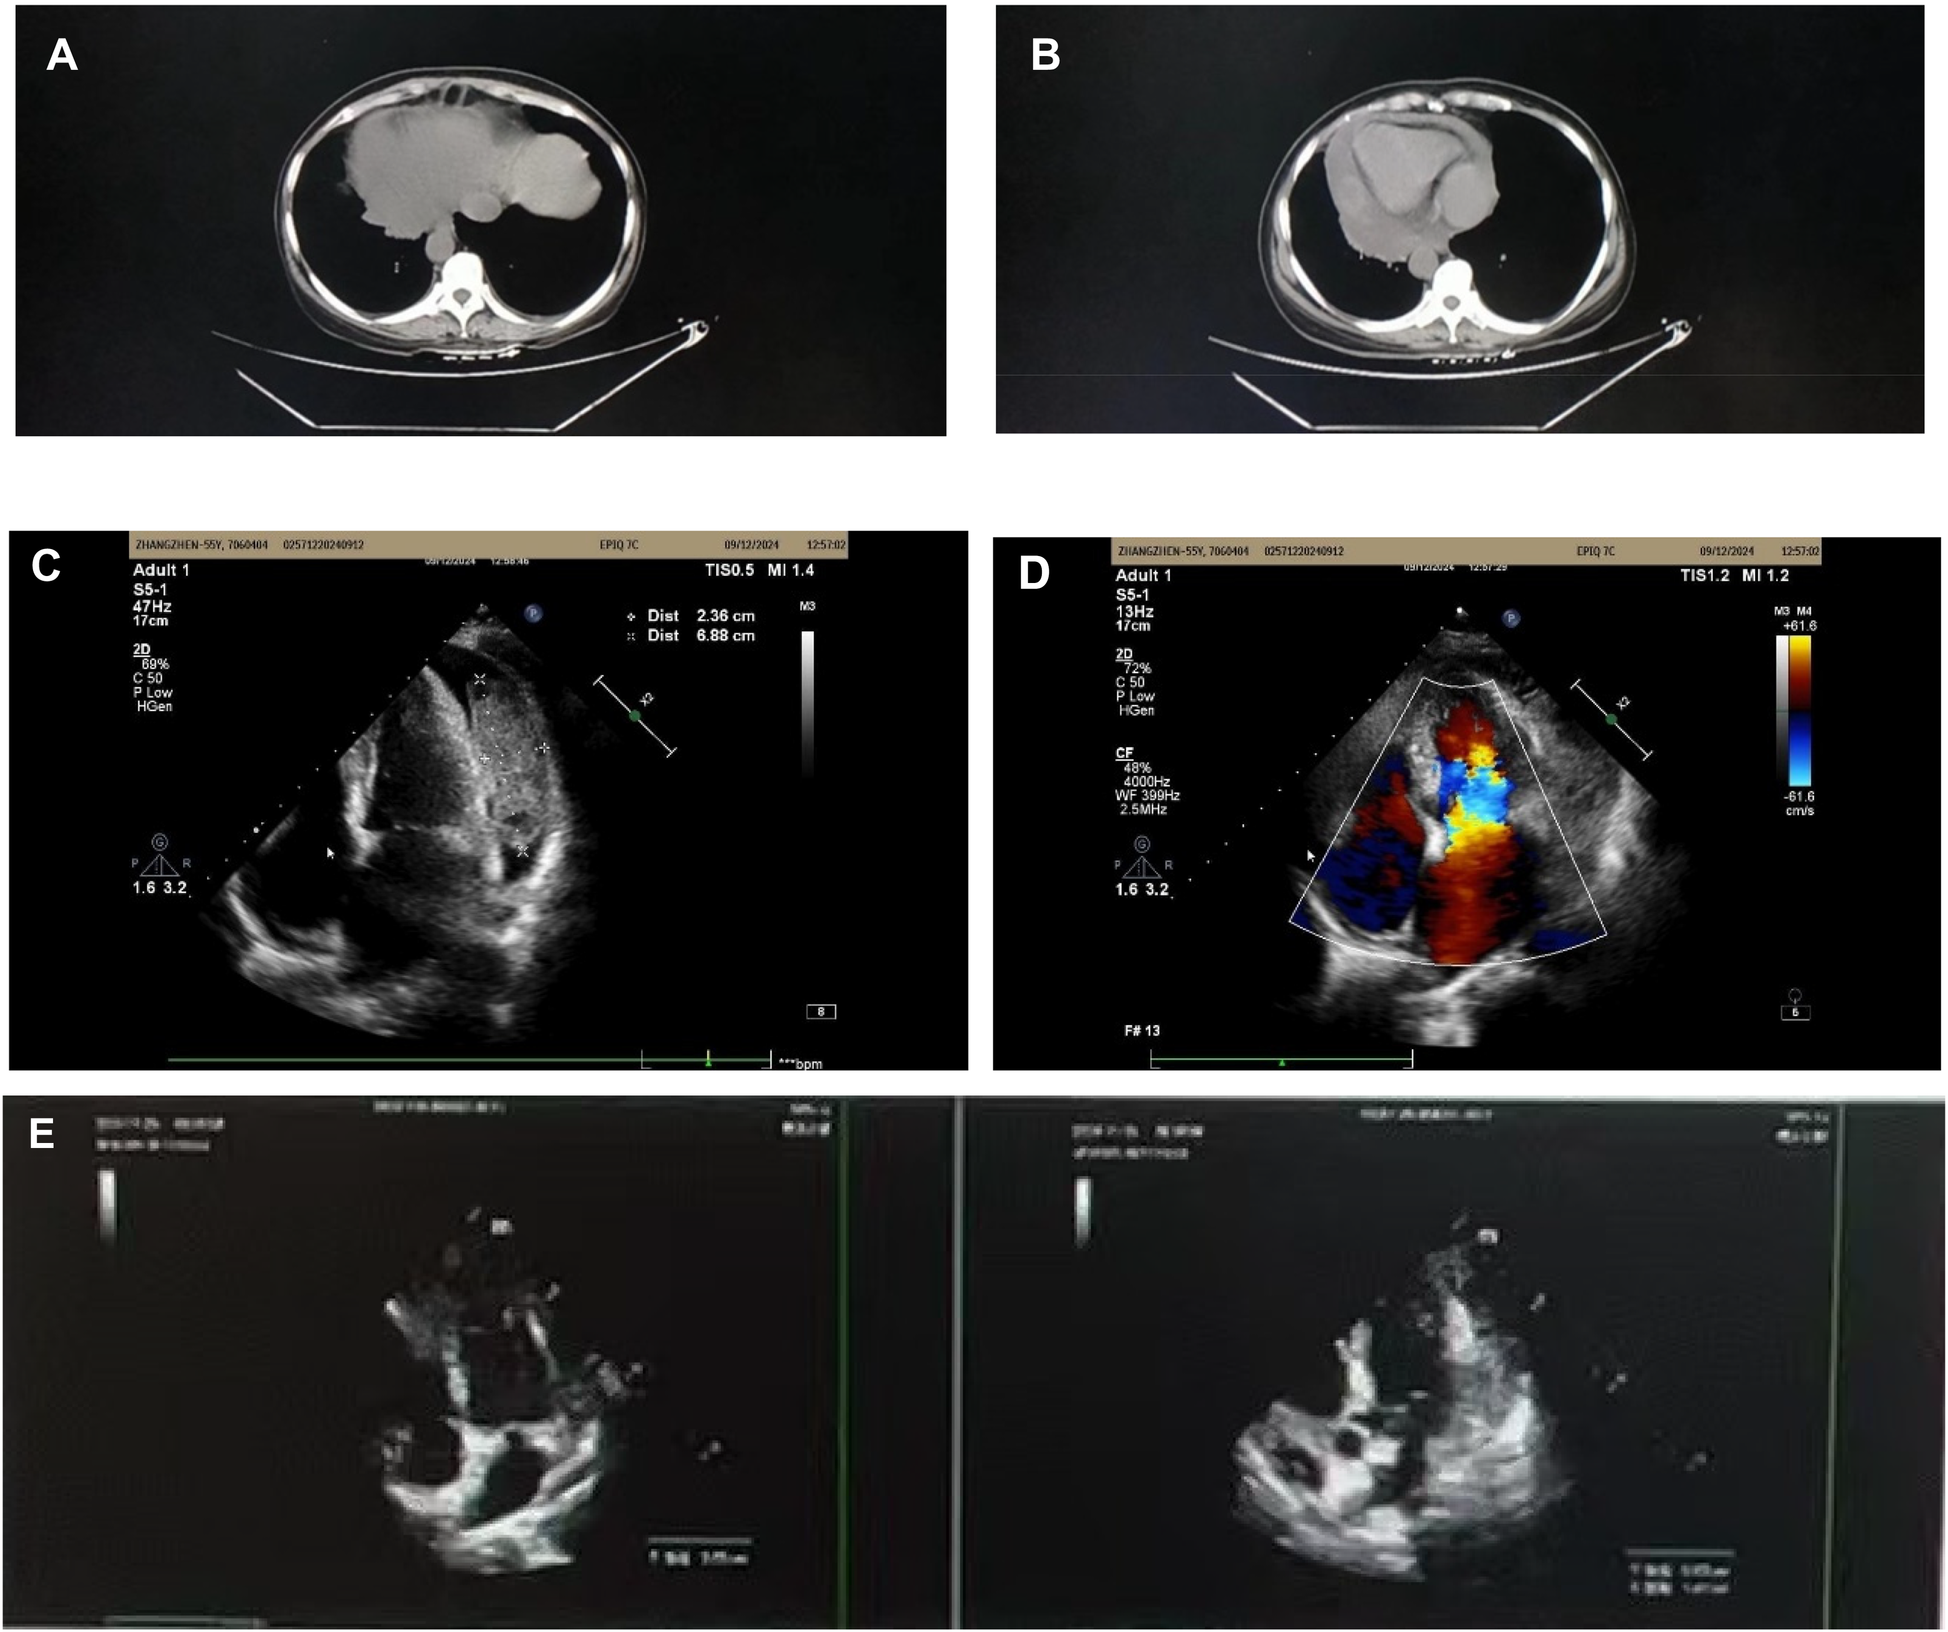

Complete blood count on admission showed no leukocytosis (6.38 × 103/μl), microcytic hypochromic anemia with hemoglobin of 9.6 g/dl, and c-reactive protein counts 243.5 mg/L. Other abnormal indicators include C-reactive protein 243.5 mg/L, procalcitonin 0.084 ng/ml, erythrocyte sedimentation rate 103 mm/60 min, and D-dimer 5,170 ng/ml. ANCA related indices, ENA enzyme profiling, COVID-19 test, A-flow and B-flow serologies were negative and tumor marker tests showed no obvious abnormality. Chest CT suggested a pericardial effusion associated with bilateral pleural effusions (Figures 1A,B), and further echocardiography was performed to identify a pericardial effusion with an irregular mass (Figures 1C,D). Levofloxacin and azithromycin were administered since the onset of fever with poor results. She was referred to cardiology for a definitive diagnosis. Considering neoplastic or tuberculous causes, PET-CT was performed to visualize multiple left pericardial masses with nodular soft tissue foci; bilateral pleural effusions. Malignant mesothelioma or infectious pericarditis could not be excluded.

Figure 1

(A) Bilateral pleural effusion. (B) Pericardial effusion. (C,D) Pericardial effusion with multiple masses. (E) 6-month follow-up echocardiogram.

After treatment with hormones in combination with anti-tuberculosis drugs, the patient was examined with chest CT and cardiac ultrasound (Figure 1E), which showed that the pleural effusion had disappeared and several pericardial masses had been resorbed (approximate range 1.4*6.6) compared with the previous ones (approximate range 2.4*6.9).